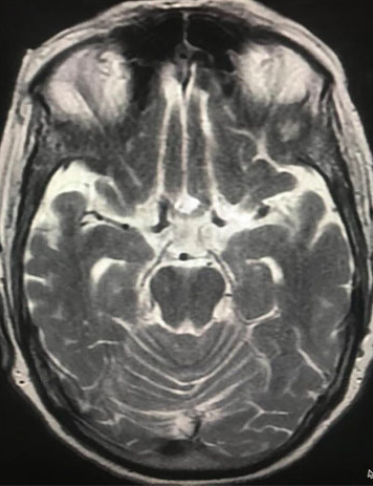

– High-resolution MRA (Magnetic Resonance Angiography)

– CT Angiography for detailed vessel visualisation

– Digital Subtraction Angiography for precise diagnosis